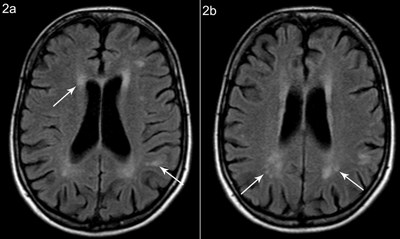

Figure 2

Patient A, axial FLAIR weighted images at different sections show (a) periventricular white matter hyperintensity and multiple hyperintense lesions in the subcortical white matter, with partial confluence and (b) white matter hyperintensity posterior and superior to the trigone.